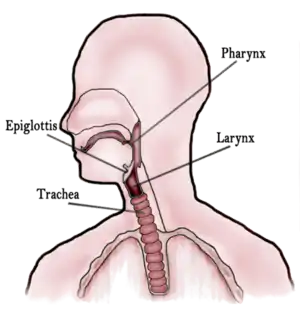

In vertebrate anatomy, the throat is the front part of the neck, internally positioned in front of the vertebrae. It contains the pharynx and larynx. An important section of it is the epiglottis, separating the esophagus from the trachea (windpipe), preventing food and drinks being inhaled into the lungs. The throat contains various blood vessels, pharyngeal muscles, the nasopharyngeal tonsil, the tonsils, the palatine uvula, the trachea, the esophagus, and the vocal cords.[1][2] Mammal throats consist of two bones, the hyoid bone and the clavicle. The "throat" is sometimes thought to be synonymous for the fauces.[3]

It works with the mouth, ears and nose, as well as a number of other parts of the body. Its pharynx is connected to the mouth, allowing speech to occur, and food and liquid to pass down the throat. It is joined to the nose by the nasopharynx at the top of the throat, and to the ear by its Eustachian tube.[4] The throat's trachea carries inhaled air to the bronchi of the lungs. The esophagus carries food through the throat to the stomach.[5] Adenoids and tonsils help prevent infection and are composed of lymph tissue. The larynx contains vocal cords, the epiglottis (preventing food/liquid inhalation), and an area known as the subglottic larynx, in children it is the narrowest section of the upper part of the throat.[6][7]